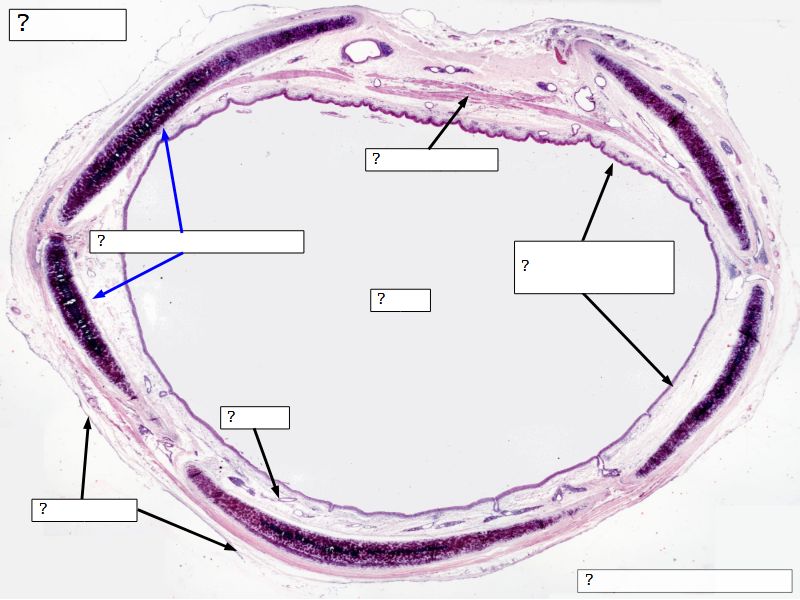

Fill in all the missing labels, and assess as you move through the slides. Answers on the down slide. It is important to do this using pen and paper, and not just glance through the images.